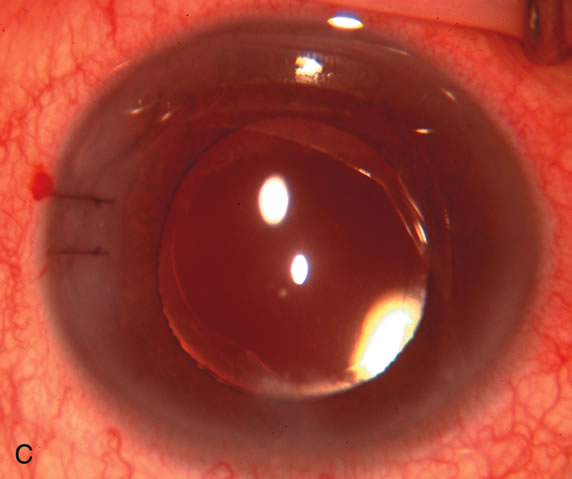

Fig. 3. Partial bleb failure following clear corneal phacoemulsification with foldable IOL. A. Preoperative bleb appearance prior to temporal lens extraction. Preoperative IOP was 12 mm Hg on no antiglaucoma medications. Time from 5-FU trabeculectomy surgery to lens extraction was one year. B. Bleb appearance 2 months after clear corneal cataract surgery with topical anesthesia. Following lens extraction, increased vascularity was noted along with decreased size of the filtering bleb. IOP increased to 20 mm Hg as early as 2 weeks after surgery, necessitating topical antiglaucoma therapy. C. High magnification view of bleb before lens extraction demonstrates diffuse pale bleb. D. High magnification view of bleb 2 months after surgery. There are vessels surrounding the nasal side of the bleb and the overall bleb size is smaller.

Cataract extraction by any technique performed in a patient with a pre-existing filter will have an effect on the previous filtering bleb.121–124 Bleb failure is more likely with ECCE compared with small-incision phacoemulsification.125 However, even patients undergoing topical anesthesia with clear corneal phacoemulsification and foldable IOL may experience bleb failure. One of three patients with a functioning filter and preoperative mean IOP of 12 mm Hg without antiglaucoma medications experiences bleb failure after lens extraction (Table 2). These patients require long-term drug therapy or bleb needling to control IOP. 126 Additional incisional glaucoma surgery may eventually be required in up to 10% of patients.127 Intraoperative iris manipulation may cause significant breakdown of the blood–aqueous barrier, resulting in inflammation that causes bleb failure. Even after uncomplicated clear corneal phacoemulsification, IOP may increase an average of 2 to 3 mm Hg due to bleb fibrosis.128 Approximately 20% of filtered patients require a long-term increase in glaucoma medications following uncomplicated clear corneal phacoemulsification with a foldable copolymer acrylic IOL129 (Fig. 3). In situations in which the bleb is not working at all, the eye will have a postoperative pressure spike that mimics that in the patient not having had a prior filtering procedure. In situations in which the bleb is marginal, the pressure spikes tend to be lower, and the final postoperative IOP tends to be around 50% higher than it was preoperatively. These patients require combined procedures in order to reestablish long-term filtration. In situations in which the bleb is very thin, polycystic, and associated with an IOP around 5 to 8 mm Hg on no antiglaucoma therapy; uncomplicated cataract extraction will have a minimal effect on the level of IOP. Patients with functioning glaucoma drainage implants usually have minimal long-term changes in IOP after uncomplicated cataract extraction.130